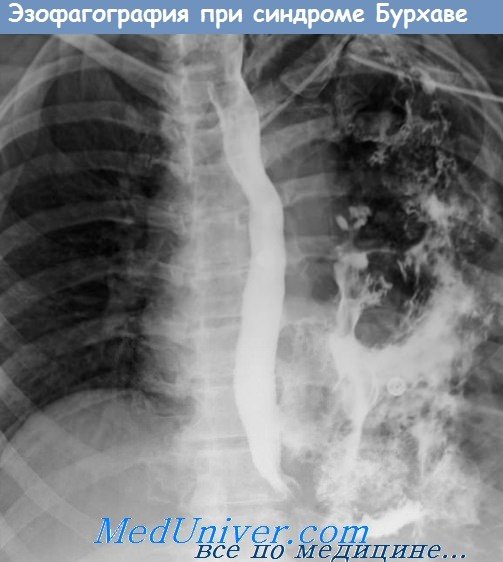

Методи діагностики

Основа діагностики

- Рентген або КТ

- Ендоскопія